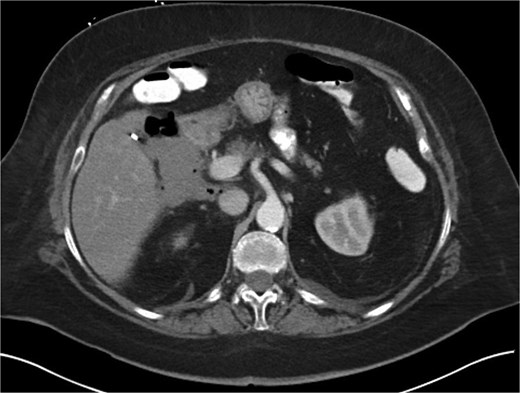

A 70-year-old woman with obesity, non-insulin-dependent diabetes, gastroesophageal reflux disease (GERD), cholecystectomy, and prior RYGB presented to the ED with acute chest and lower abdominal pain. The pain began 1 day earlier and initially responded to Ibuprofen, which she had been taking 4–6 times daily for musculoskeletal discomfort. Her pain worsened, radiating to her back, and was accompanied by belching and vomiting with dry heaving. She denied trauma or changes in bowel habits. Initial CT (Fig. 1) imaging showed a moderate hyperdense area around the duodenum, distension of the afferent limb and excluded stomach, and expected postoperative changes. She was admitted for conservative management. Four days later, a repeat CT (Fig. 2) was performed due to persistent symptoms, revealing free fluid in the intraperitoneal and retroperitoneal spaces, raising concern for duodenal perforation. She developed lethargy and diffuse abdominal tenderness and was taken to the operating room. Exploratory laparotomy with peritoneal washout, enterolysis, partial omentectomy was performed. It revealed two 1 cm posterolateral perforations of D3, which were repaired with an omental pedicle flap. The Roux limb was healthy, the jejunojejunostomy was dilated but patent, and the biliopancreatic limb was intact. Due to high vasopressor requirements, a temporary abdominal closure device was placed, and she was transferred to the surgical ICU. After stabilization, a second-look laparotomy was performed the next day to reinforce the duodenal closure, place a gastrostomy tube for drainage, and insert a J-tube for feeding (Figs 3 and 4). The abdominal wall was closed. On postoperative day 2, a CT with contrast showed extravasation from the duodenal repair site. Interventional radiology placed a transhepatic biliary drain to divert bile and support duodenal patch healing. Helicobacter pylori antigen was negative. Her condition improved, and she was started on an enteral and slow oral feeding regimen. However, at this juncture, the patient declined further treatment and requested comfort care measures.

Intra-operative image showing primary repair of D3 duodenal perforation.